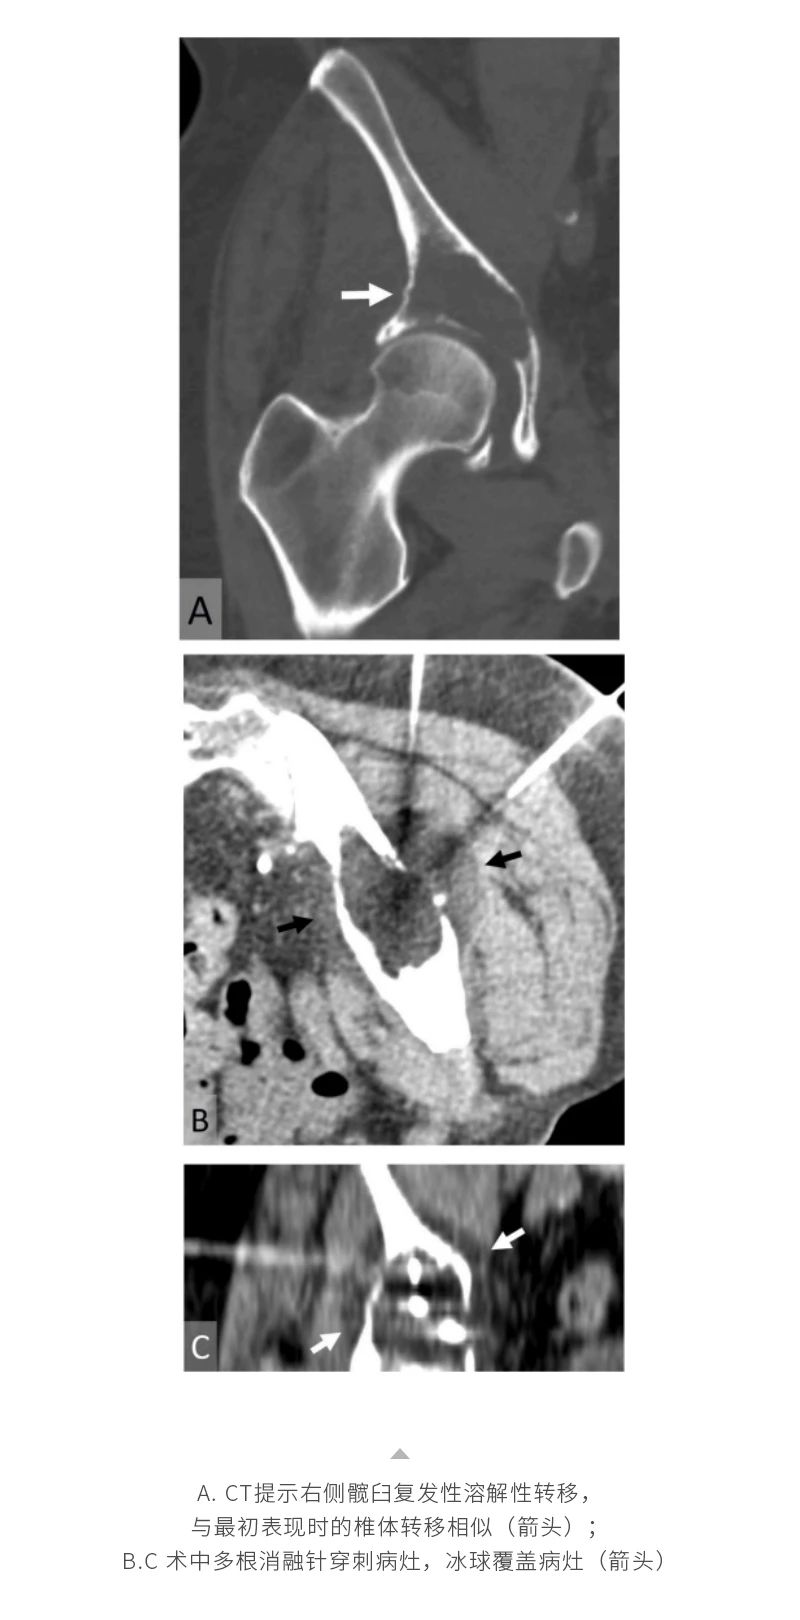

ELF ? 復(fù)合式冷熱消融系統(tǒng)